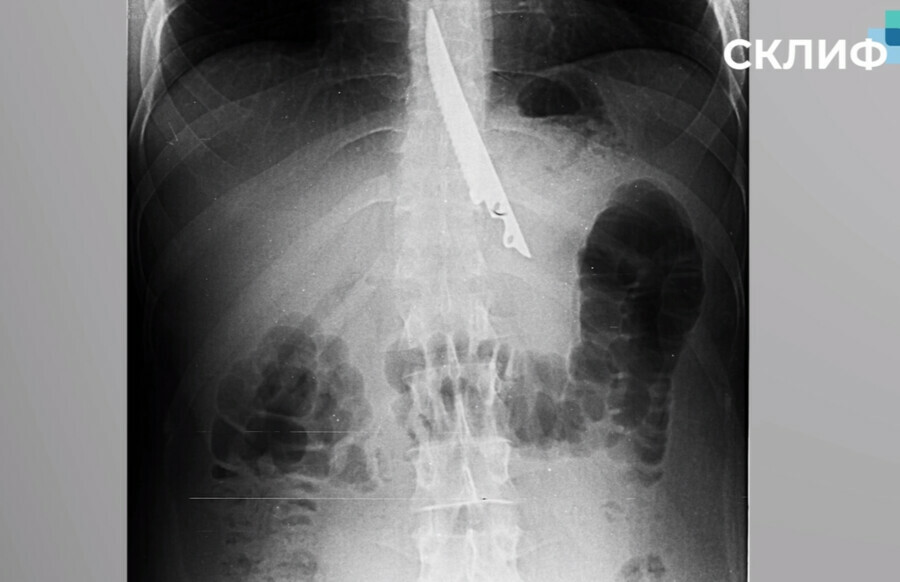

В Москве врачи чудом спасли мужчину, который случайно проглотил нож, сообщили в пресс-службе НИИ имени Склифосовского. Инцидент произошел, когда мужчина в компании друзей на отдыхе жарил шашлык.

Он подавился куском мяса, а его окружение не придумало ничего лучше, как протолкнуть еду 20-сантиметровым ножом. В итоге шашлычник случайно проглотил острый предмет. Врачи Склифа извлекли его, проведя операцию.